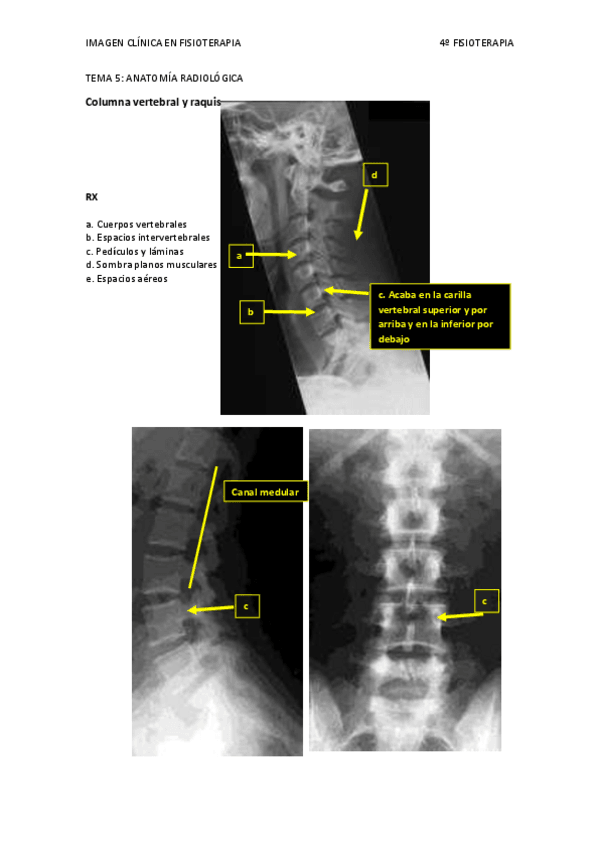

He publicado nuevos apuntes de 4º IMAGEN CLÍNICA EN FISIOTERAPIA: TEMA 5.pdf

5 páginas